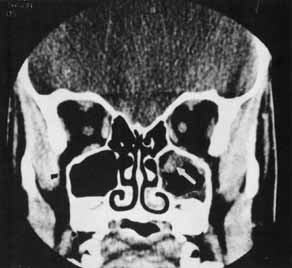

Of the adjunctive tests available, CT scan is the most useful in providing information about the presence and position of a foreign body relative to other structures in the orbit. Steel fragments 0.5 mm in diameter or larger74 and steel particles as small as 0.06 mm3 can be detected.75 Density measurements can be analyzed to distinguish metal, wood, glass, and air from surrounding tissue (Fig. 18). The appearance of wood may vary with the length of time in the orbit and the degree of hydration.76 In some cases, CT has not been able to detect wooden foreign bodies.77 Localization can best be achieved with the evaluation of axial and coronal views. Additional sagittal interpretations and three-dimensional reconstructions can be generated with available software.74 The diagnostic limitations of CT scans must be recognized; in some situations, accurate localization may be obscured by scatter artifact caused by metals or false-negative findings of radiolucent materials.

Fig. 18 A, Wood foreign body (arrow). B, Glass foreign body (arrow). C, Metal foreign body (arrow).